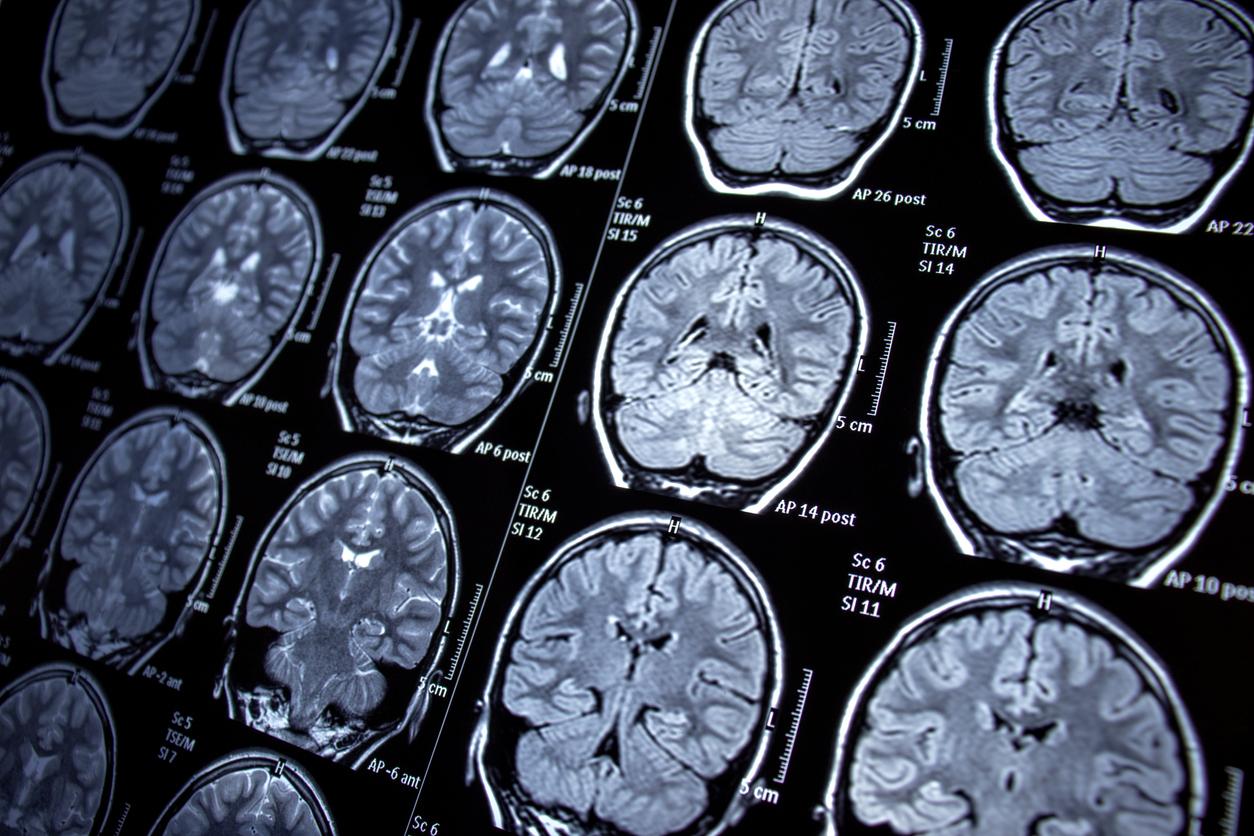

Ces dernières années, de plus en plus de nouvelles pathologies font leur apparition. Récemment, des chercheurs américains et canadiens ont identifié une nouvelle maladie neurologique rare chez trois enfants, deux frères et sœurs et "un enfant non apparenté". Dans un rapport, ils indiquent que les jeunes patients souffraient tous de problèmes de coordination motrice et de la parole, et l'un d'entre eux présentait des anomalies du cervelet, la partie du cerveau impliquée dans les mouvements complexes.

Les scientifiques ont également constaté que les enfants présentaient tous des mutations dans les deux copies du gène ATG4D. Ce dernier contribue à l’autophagie, "un processus dynamique et hautement conservé qui régule la décomposition et le recyclage des composants cellulaires". L’autophagie est utilisée par les cellules de tout l'organisme, mais les neurones y sont particulièrement dépendants, car ce processus leur permet de survivre. "Cependant, on sait peu de choses sur la façon dont l'ATG4D contribue à la santé des neurones", a déclaré l’équipe.